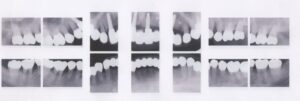

40歳・男性

初診日 2016. 12.  (5年経過症例)

1年前から他の歯科医院にて部分的な治療を受けたが、どんどん歯が悪くなって、見た目が良くない・噛めないとのことで再治療を希望された。昨日、上の前歯が自然に取れた、他の医院に行こうとしたところ知人に当医院を勧められ来院した。アングルクラスⅡであった。

治療法

全顎的に歯周病が進行し、ほとんどの歯に動揺が見られた。アングルクラスⅢで下顎前歯部に叢生が見られ、全顎の再生療法の後に、全顎的にオールセラミッククラウンを装着し、既存の被せのやり直しを行なった。

治療結果

審美的な仕上がりで、患者自身も満足した。5年経過し良好である。

現在は2〜3ヶ月おきのメインテナンス中である。